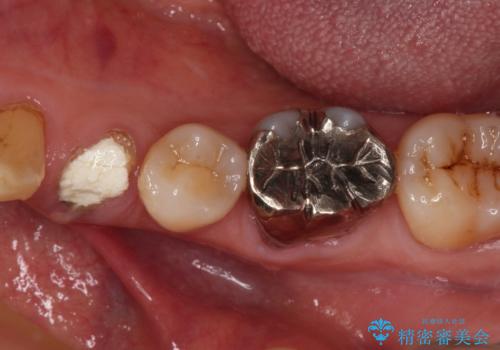

- 近医にて抜歯が必要と言われたとのことで来院された患者様です。

顕微鏡下で確認したところ、歯根に及ぶ破折線が認められたため、抜歯を行うこととしました。

インプラント治療をお勧めしましたが、取り扱いや手入れが煩雑でも良いとのことで、可撤性義歯(入れ歯)にて補綴治療を行うこととしました。